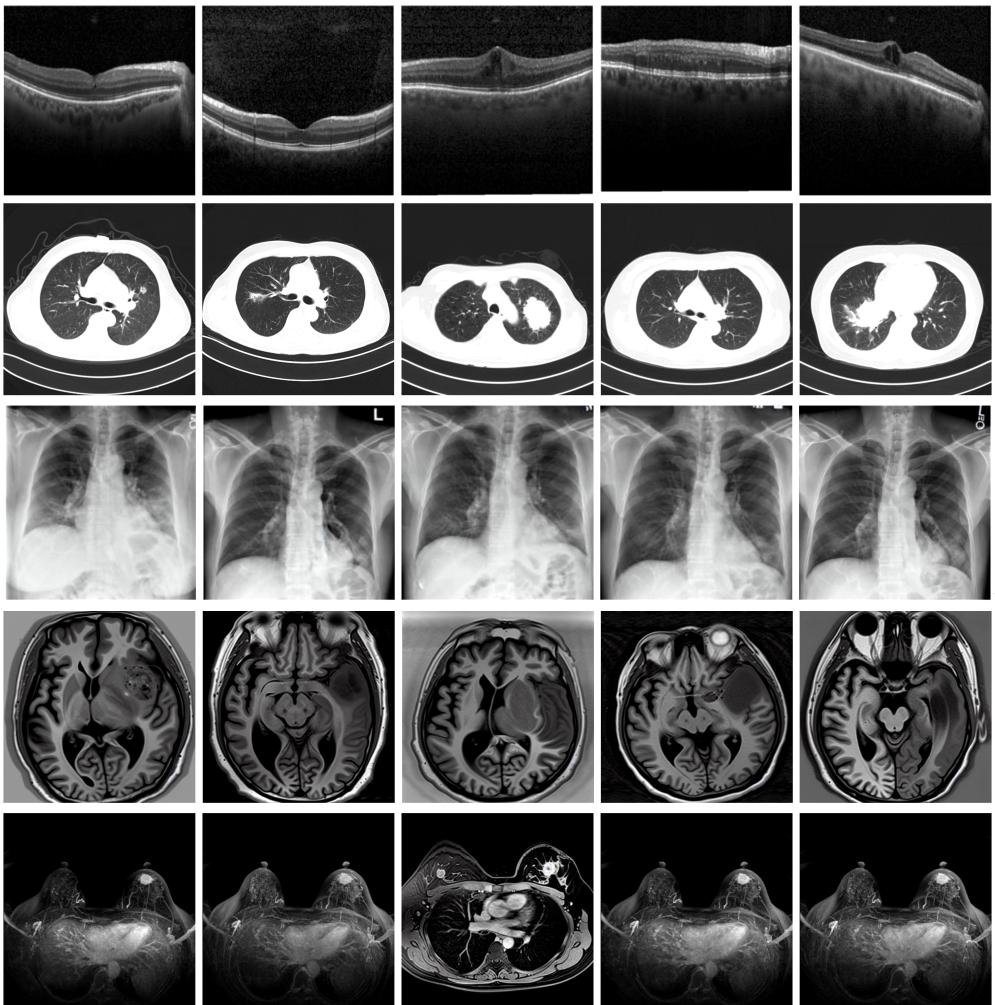

圖為由MINIM生成的高質(zhì)量醫(yī)學(xué)合成圖像(受訪者供圖)

“目前公開的醫(yī)學(xué)影像數(shù)據(jù)非常有限,我們建立的生成式模型有望解決訓(xùn)練數(shù)據(jù)不夠的問(wèn)題。”北京大學(xué)未來(lái)技術(shù)學(xué)院助理研究員王勁卓說(shuō),研究團(tuán)隊(duì)利用多種器官在CT、X光、磁共振等不同成像方式下的高質(zhì)量影像文本配對(duì)數(shù)據(jù)進(jìn)行訓(xùn)練,最終生成海量的醫(yī)學(xué)合成影像,其在圖像特征、細(xì)節(jié)呈現(xiàn)等多方面都與真實(shí)醫(yī)學(xué)圖像高度一致。

實(shí)驗(yàn)結(jié)果顯示,MINIM生成的合成數(shù)據(jù)在醫(yī)生主觀評(píng)測(cè)指標(biāo)和多項(xiàng)客觀檢驗(yàn)標(biāo)準(zhǔn)方面達(dá)國(guó)際領(lǐng)先水平,在臨床應(yīng)用中具有重要參考價(jià)值。在真實(shí)數(shù)據(jù)基礎(chǔ)上,使用20倍合成數(shù)據(jù)在眼科、胸科、腦科和乳腺科的多個(gè)醫(yī)學(xué)任務(wù)準(zhǔn)確率平均可提升12%至17%。